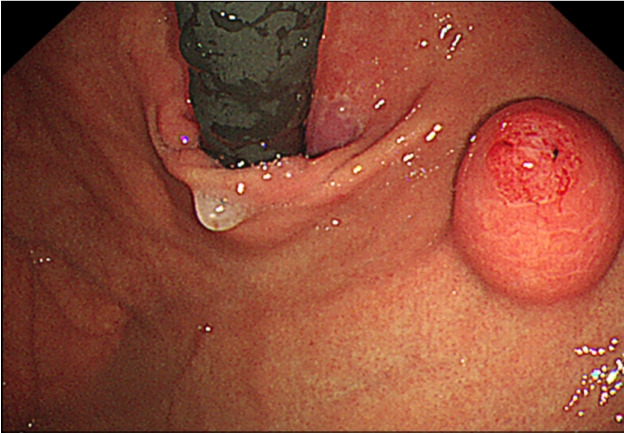

胃上皮下肿瘤(set)通常是无症状的,经常在内镜检查中偶然发现。胃内翻性增生性息肉(IHP)的特征是增生性粘膜向下生长到粘膜下层。由于这些特点,胃IHP经常被误诊为SET。胃ihp在大多数情况下是无症状的,是偶然发现的。值得注意的是,IHPs可能伴有腺癌或贫血,这是由于与这种病变相关的慢性出血;因此,建议内镜下粘膜下剥离术完全切除直径为bbbb2 cm的ihp。我们报告一个病例的胃IHP是在筛选内镜诊断在一个无症状的病人。我们观察到从SET中表达的白色化脓性渗出物,内窥镜超声检查显示SET起源于肌层粘膜。内镜下粘膜剥离术去除SET,最终组织病理学结果显示胃IHP。本病例报告强调,与白色渗出物相关的SET患者应怀疑ihp。

Gastric subepithelial tumors (SETs) are usually asymptomatic and are often detected incidentally during screening endoscopy. A gastric inverted hyperplastic polyp (IHP) is characterized by downward growth of hyperplastic mucosa into the submucosal layer. Owing to these characteristics, a gastric IHP is frequently misdiagnosed as a SET. Gastric IHPs are asymptomatic in most cases and are discovered incidentally. Notably, IHPs may be accompanied by an adenocarcinoma or anemia owing to chronic bleeding associated with this lesion; therefore, endoscopic submucosal dissection is recommended for complete excision of IHPs measuring > 2 cm. We report a case of gastric IHP that was diagnosed during screening endoscopy in an asymptomatic patient. We observed a whitish purulent exudate expressed from the SET, and endoscopic ultrasonography revealed a SET originating from the muscularis mucosa. Endoscopic submucosal dissection was performed to remove the SET, and final histopathological findings revealed a gastric IHP. This case report highlights that IHPs should be suspected in patients with a SET associated with whitish exudates.